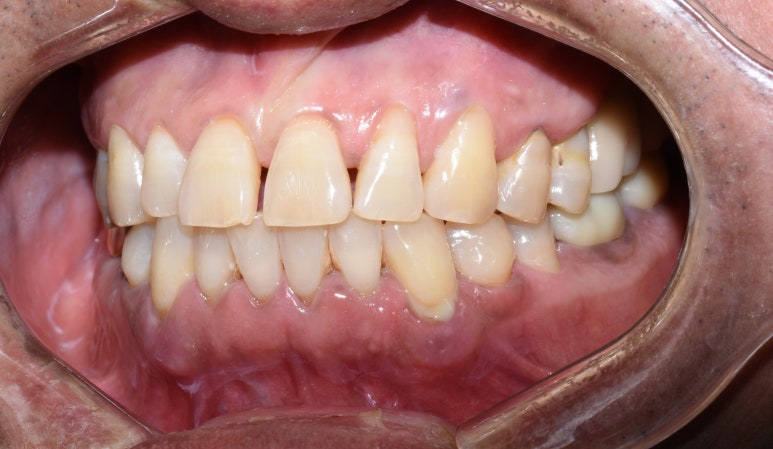

오랜 시간 치아가 방치되어 아래 파노라마와 같은 모습이었습니다.

큰 위쪽 어금니는 3개가 없고 하나는 매우 흔들리는 상태,

아래쪽 큰 어금니는 파절되고 썩어있는 상태였습니다.

엑스레이 사진에서 길이측정을 해보면 위쪽 어금니쪽에 뼈 수직길이가 2~3 미리 정도밖에 남지 않아

보통 심는 8~10미리의 임플란트를 심기위해 상악동수술(상악동거상술과 뼈이식)도 해야하는 상태였습니다.